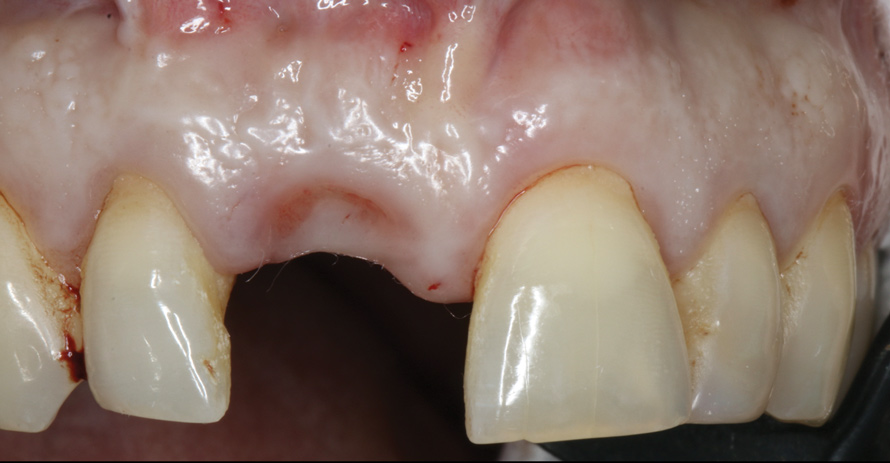

A 56-year-old female patient was referred for the evaluation of tooth No. 8 (Figure 4 and Figure 5). A periapical radiograph indicated that the tooth had undergone apicoectomy and received an excessively long post (Figure 6), and a cone-beam computed tomography (CBCT) scan of the site revealed a lack of buccal plate bone (Figure 7).

4. Facial and occlusal views of initial clinical presentation of tooth No. 8.

Figure 4

5. Facial and occlusal views of initial clinical presentation of tooth No. 8.

Figure 5